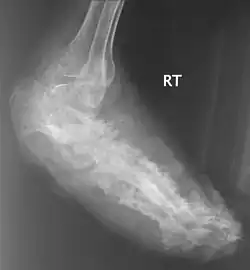

| Нога, поражённая мицетомой | |

В костях через надкостницу масса зерен постепенно может переходить в костную ткань и костный мозг, и иногда в таких случается спонтанный патологический перелом. Рентгенологическое исследование определяет множественные остеомиелитические поражения, которое можно описать как полости и периостальные образования новой костной ткани. Также иногда наблюдают остеопороз, вызываемый давлением окружающих отечных тканей и атрофию. Вследствие хронического периостального фиброза суставы иногда тугоподвижны. При мицетомах черепа наблюдали диффузное истончение костей, вызванное давлением кожных образований и иногда трабекулы, в некоторых местах, хотя и очень редко, могут быть и небольшие области остеолиза.

Для диагностики мицетомы обычно используют рентгеновские снимки, УЗИ, аспирационную пункционную биопсию. Выбор метода зависит от выделения возбудителя и эндемических мест инфекции.